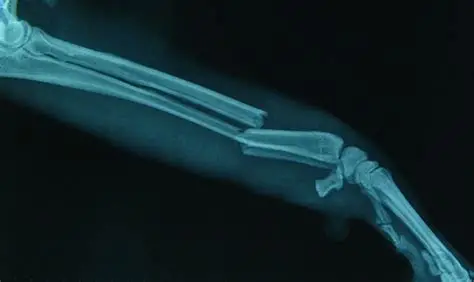

Новаторска медицинска иновация от Китай променя начина, по който лекарите лекуват фрактури на кости.

Учените разработиха революционно лепило, което може да възстанови счупените кости само за три минути с едно инжектиране.

Това костно лепило е изработено от усъвършенствани биоматериали, предназначени да имитират естествената костна структура на тялото. След като се инжектира, то се втвърдява бързо и свързва счупените костни сегменти заедно, осигурявайки мигновено срастване. За разлика от традиционните отливки, метални плочи или винтове, този метод свежда до минимум болката, ускорява възстановяването и намалява риска от усложнения.